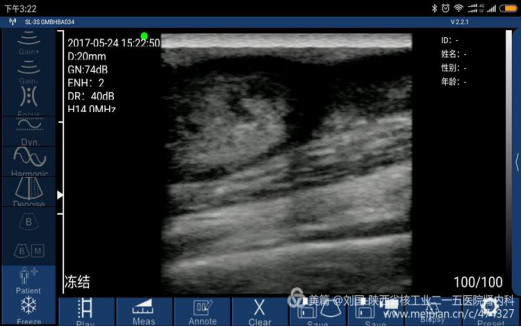

Result checked by Sonostar’s wireless ultrasound, and displayed by my mobile phone-Mi max

Cephalic vein condition checked by Sonostar’s wireless ultrasound, and displayed by my mobile phone-Mi max